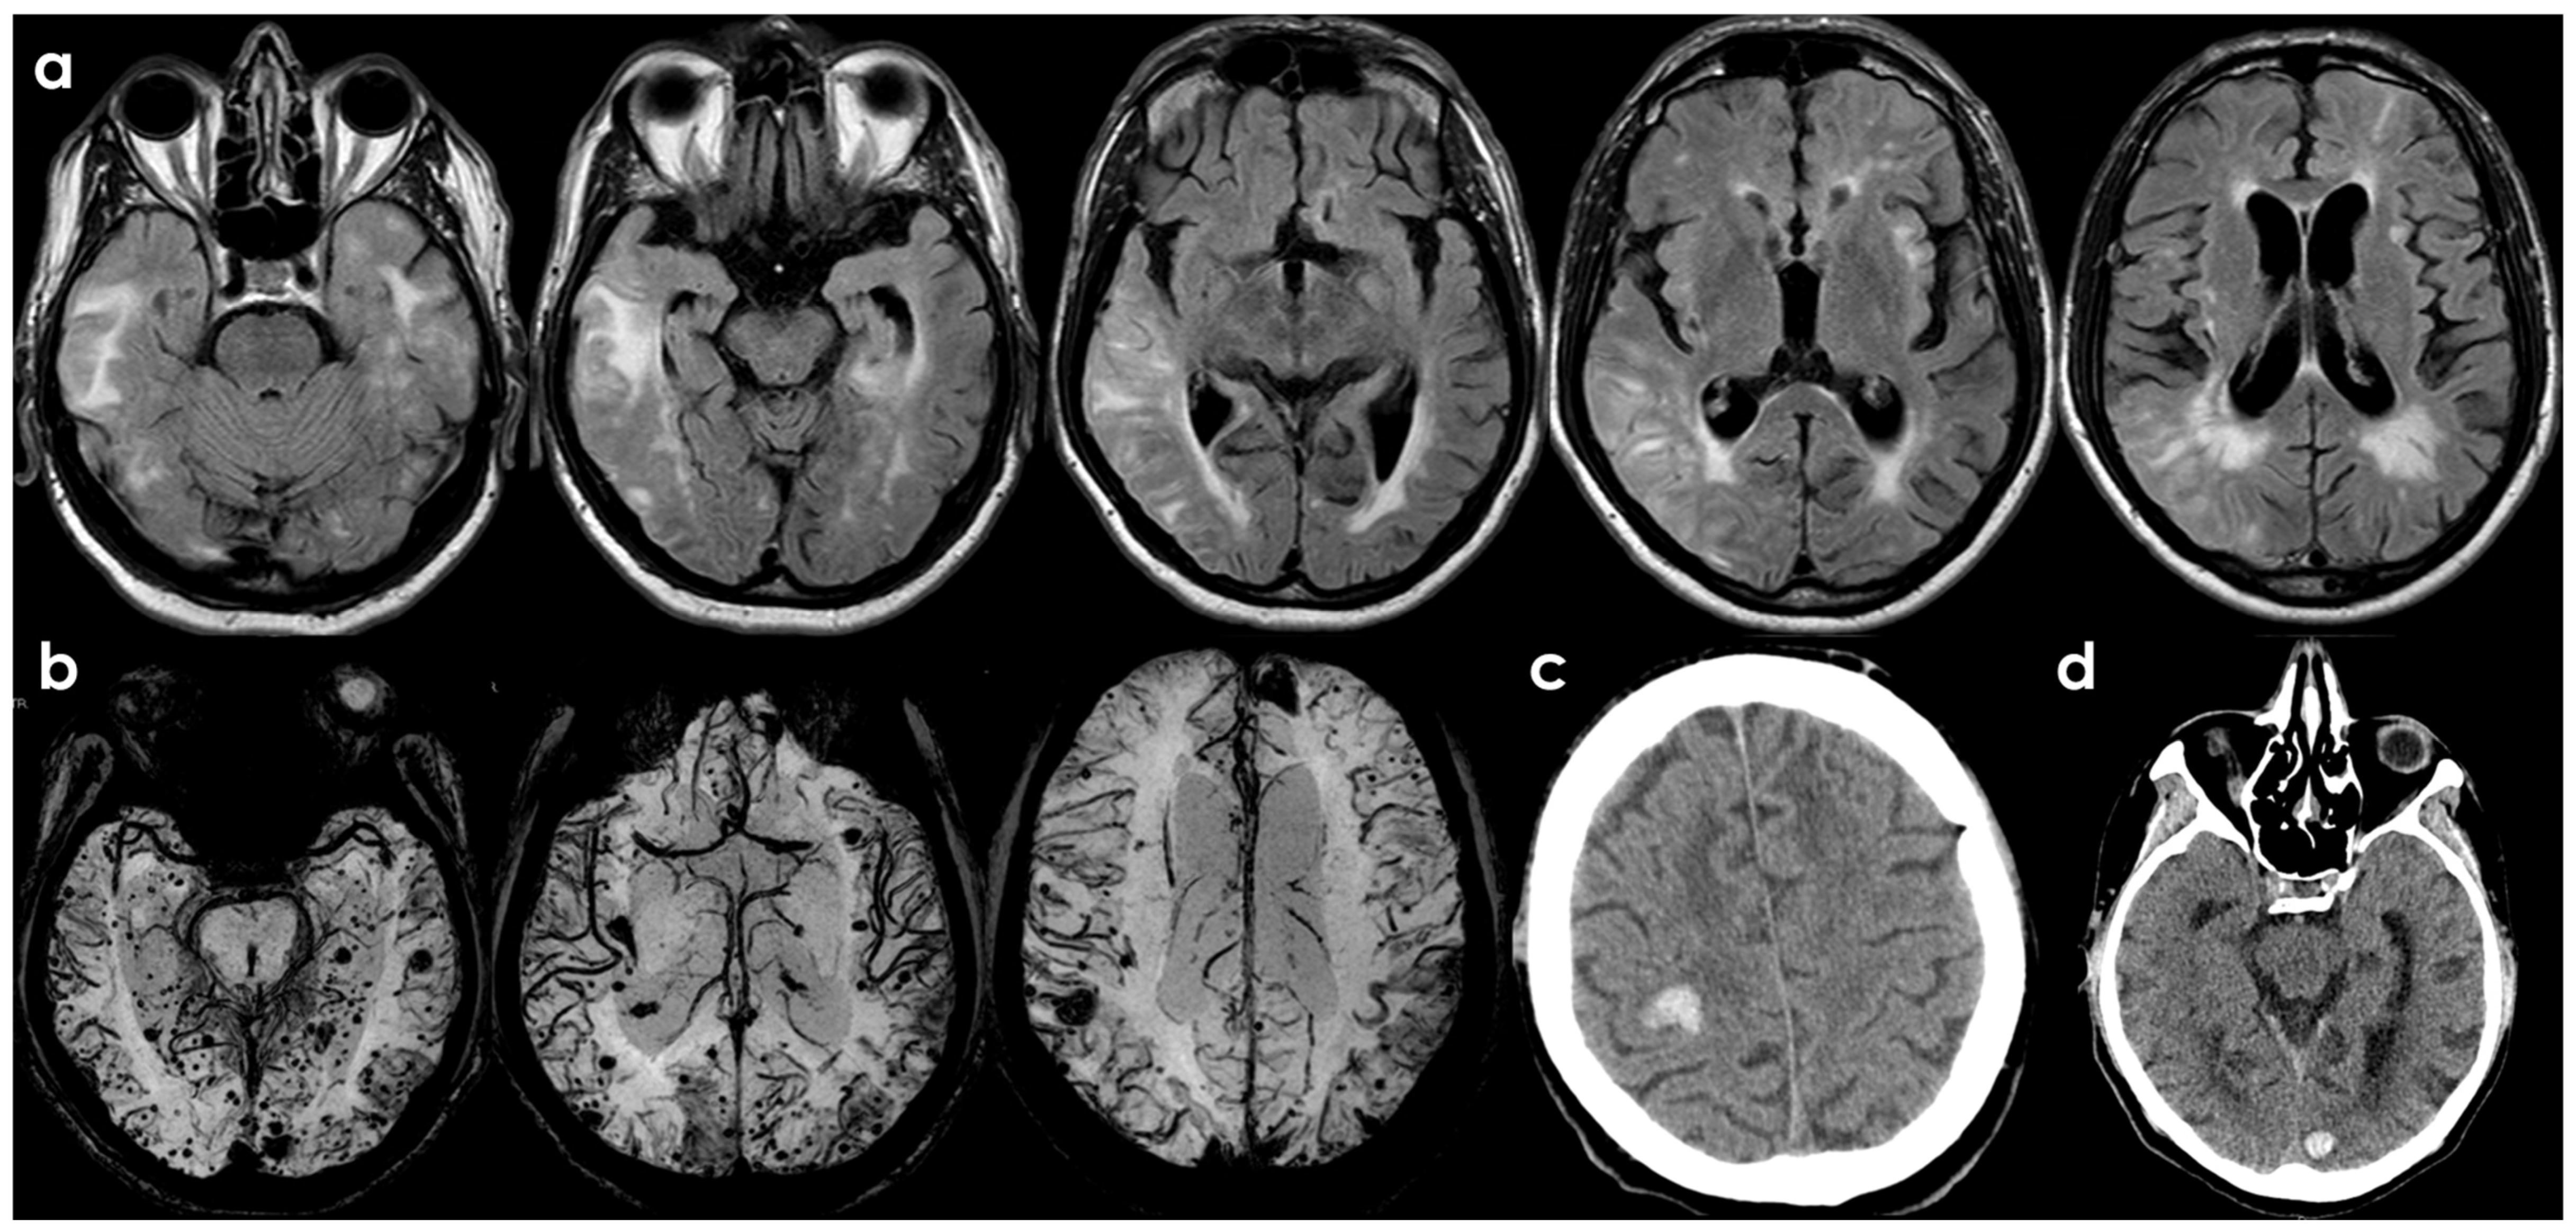

- ARIA-E (Edema/Effusion), characterized by focal regions of white matter hyperintensities (WMH), or increased signal intensities within the cortical sulci, reflecting the accumulation of protein-rich fluid within the leptomeningeal and sulcal spaces, consistent with an exudative inflammatory process.

- ARIA-H (Hemorrhage), defined by the appearance of CMB, cSS, or Intracerebral Hemorrhage (ICH). These findings are thought to arise from lesions related to CAA, as a result of the weakening of vessel walls and their subsequent rupture.

| Neuroimaging characteristics | CAA-ri is usually characterized by: -Unifocal or multifocal hyperintense lesions (cortico-subcortical or deep) that are asymmetric and extend to the immediately subcortical white matter -Presence CMB or cSS, frequently colocalized with ARIA-E Although not included in the CAA-ri diagnostic criteria, leptomeningeal involvement similar to the drug-induced counterpart have been described. | ARIA-E may present as parenchymal edema, sulcal effusion, or a combination of both. The imaging pattern is similar to vasogenic edema, represented by hyperintense signal on T2-FLAIR in the white matter, gray matter, or both. There may be associated local mass effect and gyral swelling. ARIA-H includes CMB, cSS (frequently colocalized with ARIA-E), or lobar ICH. |